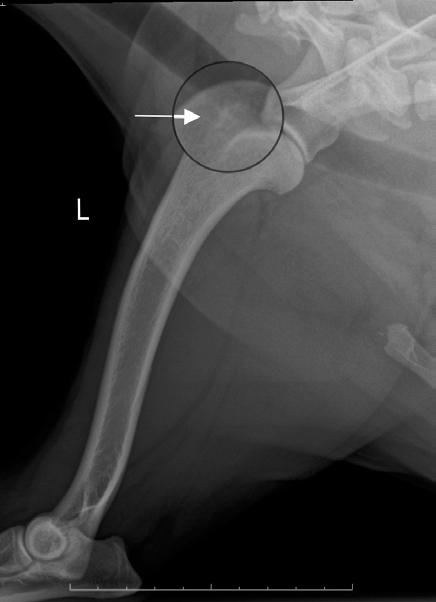

Placarea osoasă a fost folosită ca metodă de gestionare a fracturilor încă de la sfârșitul anilor 1800. Primele plăci de osteosinteză au fost aplicate în chirurgia umană de Carl Hansman în 1886 – figura 12, plăci de nichel acoperite cu oțel, de Halstead în 1893 – figura 13, care folosește o placă de argint și respectiv de Lane în 1895, cu plăci de oțel – figura 14.

În 1907, Albin Lambotte (1866-1955) introduce termenul de osteosinteză. Iar, în 1909, în studiul său axat pe studiul plăcilor din aliaje ca aluminiu, argint, cupru și magneziu, arată că acestea sunt deformabile și corodabile, propunând plăcile din oțel moale placat cu aur sau nichel

– figura 15. Figura 11.Tije zăvorâte (blocate) – A; secțiune longitudinală printr-un montaj cu tijă zăvorâtă într-o fractură de diafiză femurală – B și C (Din http://cal.vet.upenn.edu/projects/orthopod/csfr/terms/ilnapplication.htm) Figura 12. Carl Hansman (1853-1917). Pictură murală de Johannes Grützke în clădirea administrativă a Berufsgenossenschaftlische Unfallkrankenhaus, Hamburg, Germania: „Aus der Geschichte der Unfallchirurgie” (Din https://link.springer.com/article/10.1007/s00264-016-3347-4)